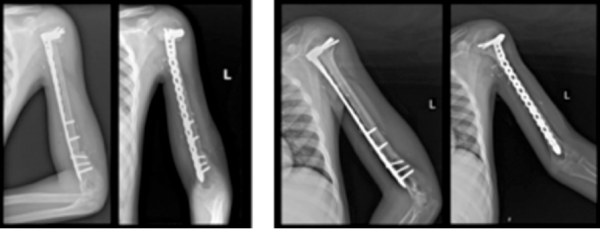

אחד החידושים בתחום הטיפול הניתוחי בממאירויות גרמיות בילדים, הוא שימוש במשתלים מתארכים. המשתלים המתארכים הראשונים הצריכו ניתוחים רבים לשם ביצוע הארכות חוזרות של המשתל. עם העלייה במספר הניתוחים, גדל גם הסיכון לסיבוכים. ישנה אפשרות לשימוש במשתלים הניתנים להארכה באופן לא ניתוחי, בעיקר באמצעות שדה מגנטי חיצוני.

פעמים רבות, טכניקות המיקרוכירורגיה מאפשרות לבצע שחזור ביולוגי, כלומר שחזור שאינו עושה שימוש במשתל תותב. לדוגמה, שחזור גרמי בעזרת שתלי עצם עצמי עם אספקת דם, שתלי עצם מסוגים אחרים, מתלי רקמה רכה עם או בלי אספקת דם, העברות גידים ואפילו העברות עצבים או שתלי עצב.

יתרונו של השחזור הביולוגי בולט במיוחד בילדים, לאור העובדה שמשך הישרדותם של משתלים תותבים הוא בדרך כלל מוגבל בהשוואה לאורך החיים הפוטנציאלי הארוך של המטופל. פעמים רבות, שחזורים בעזרת משתל מצריכים ניתוחים נוספים, לדוגמה לטיפול בסיבוכים, כגון התרופפות של המשתל, שחיקה, ולעיתים זיהום סביב משתל. שיעור הניתוחים החוזרים בשחזורים הביולוגיים הוא על פי רוב נמוך באופן משמעותי בהשוואה לשחזורים בעזרת משתל.